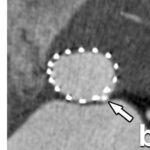

This increasingly successful method for percutaneous valve repair comes with the necessity of very precise and detailed analysis in order to plan the implant position. This can be achieved by CT and/or MRI. The European Society of Cardiovascular Radiology provides...